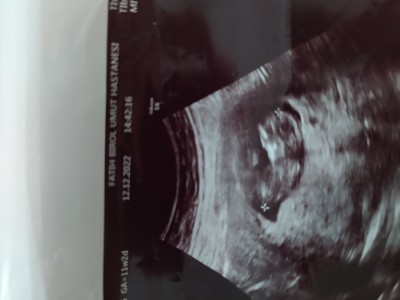

12 Aralık 2022 Hamilelikte Bebek Sağlığı kategorisinde (93 puan) sordu

Kızlar daha erken ama cinsiyet tahmini yapabilecek olan var mı biraz fazla merak ediyorum sanırım

Gebelik haftası 11+2

Çok erken cinsiyet tahmini için :)

Kıza benziyor canım